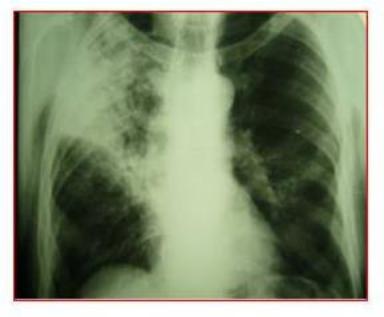

Больной Б. 24 лет обратился к врачу-терапевту участковому с жалобами на повышение температуры до 38,5 °С, кашель со скудной мокротой слизистого характера, преимущественно по утрам, одышку в покое, ночные поты. Имеет контакт с больным туберкулѐзом отцом.

Болен в течение 10 дней, когда после переохлаждения повысилась температура, появилась слабость, одышка в покое.

После рентгенологического обследования выявлена патология в лѐгких. Направлен в пульмонологическое отделение с диагнозом «внебольничная двусторонняя очаговая пневмония».

При осмотре: кожные покровы бледные, румянец щѐк, периферические лимфоузлы не увеличены. При перкуссии над лѐгкими тимпанит, дыхание ослабленное, хрипов нет.

Общий анализ крови: эритроциты - 3,3×1012/л, гемоглобин - 120 г/л, лейкоциты - 11,8×109/л, эозинофилы - 4%, палочкоядерные нейтрофилы - 14%, сегментоядерные нейтрофилы - 52%, лимфоциты - 18%, моноциты - 12%, СОЭ - 30 мм/час.

Реакция Манту с 2 ТЕ ППД-Л – отрицательная. Анализ мокроты на МБТ методом люминесцентной микроскопии – МБТ не обнаружены.

Рентгенологически: в лѐгких определяется тотальная мелкоочаговая диссеминация, очаги размерами 2-3 мм, расположены периваскулярно, средней интенсивности, с чѐткими контурами, без склонности к слиянию.

Терапия антибиотиками широкого спектра действия в течение двух недель эффекта не дала.